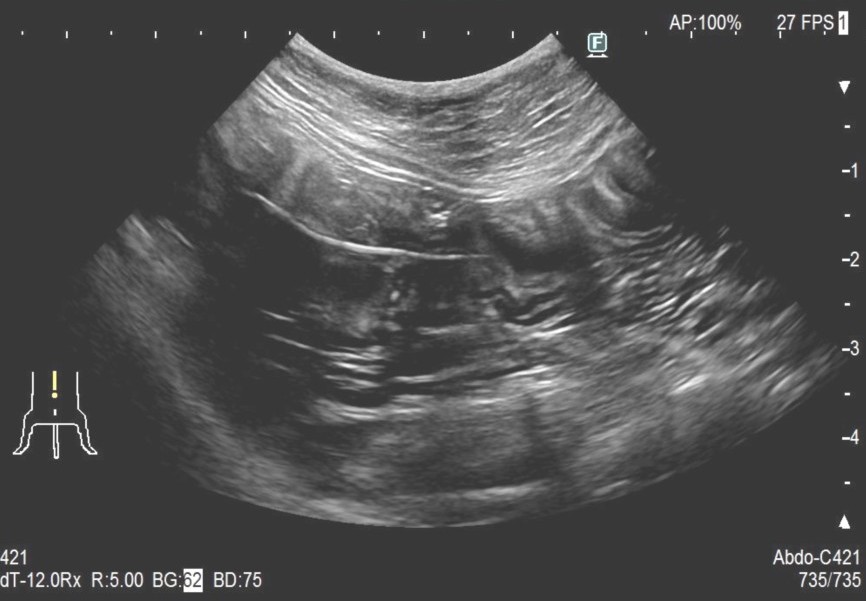

レントゲンにて胃内にX線不透過物(釣り針)、腹部エコーにてアコーディオン状に手繰り寄せられた消化管と紐状異物を確認

釣り針の誤食ならびに糸による紐状異物と診断